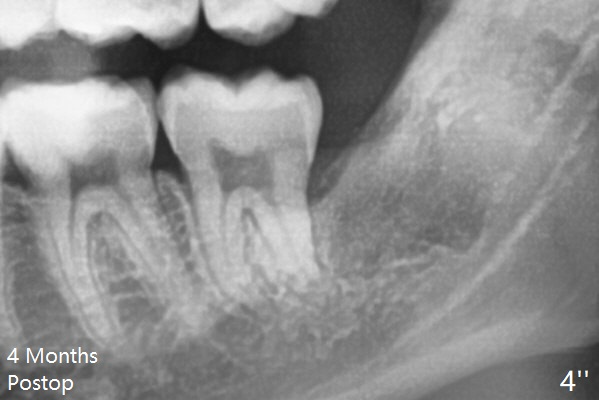

The cortical and cancellous bone seems to have formed in the #17 sockets in 4 months (Fig.4").